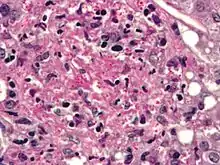

Cryptococcus neoformans can cause a severe form of meningitis and meningo-encephalitis in patients with HIV infection and AIDS. The majority of Cryptococcus species live in the soil and do not cause disease in humans. Cryptococcus neoformans is the major human and animal pathogen. Papiliotrema laurentii and Naganishia albida, both formerly referred to Cryptococcus, have been known to occasionally cause moderate-to-severe disease in human patients with compromised immunity. Cryptococcus gattii is endemic to tropical parts of the continent of Africa and Australia and can cause disease in non-immunocompromised people.[1]

Infecting C. neoformans cells are usually phagocytosed by alveolar macrophages in the lung.[11] The invading C. neoformans cells may be killed by the release of oxidative and nitrosative molecules by these macrophages.[12] However some C. neoformans cells may survive within the macrophages.[11] The ability of the pathogen to survive within the macrophages probably determines latency of the disease, dissemination and resistance to antifungal agents. In order to survive in the hostile intracellular environment of the macrophage, one of the responses of C. neoformans is to upregulate genes employed in responses to oxidative stress.[11]